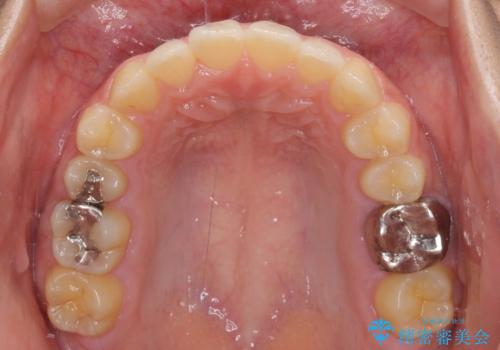

海外勤務中のインビザラインによる矯正治療

それでも、しっかりとマウスピースを装着してくださったので、大きなトラブルもなく治療を終えることができました。

- 1年6ヶ月

- 10-30回